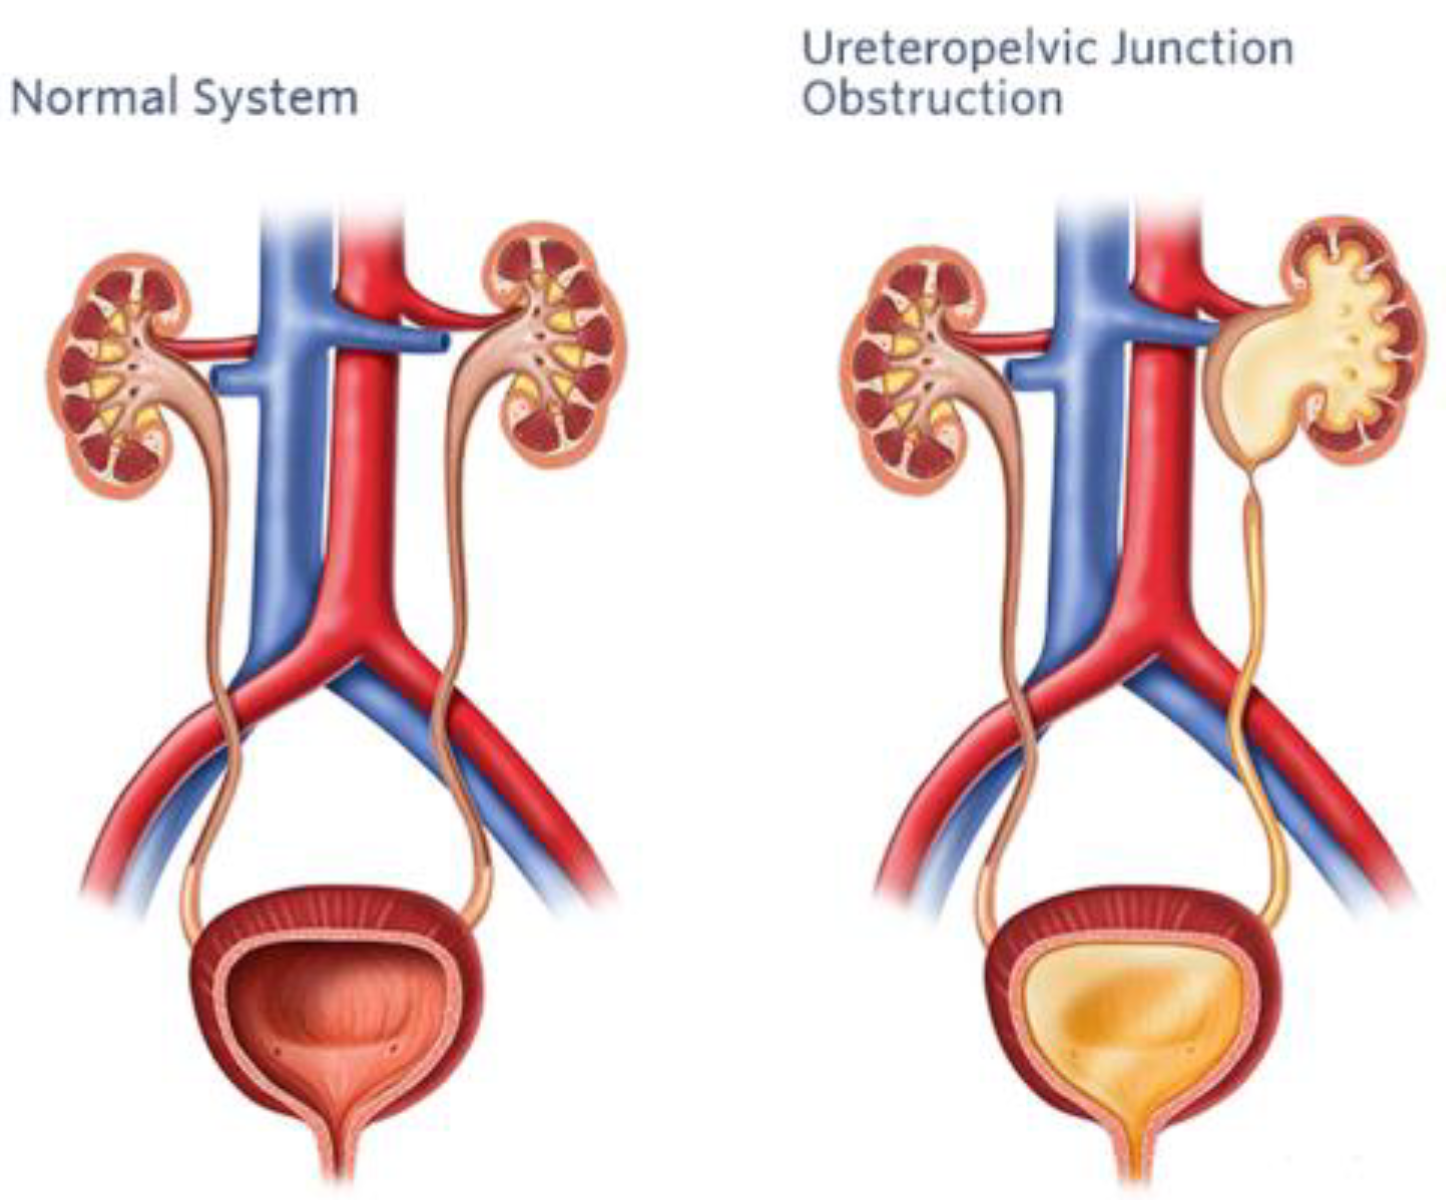

3. Pyeloplasty

3.1. Surgical Challenges in Pediatric Pyeloplasty

3.2. AI-Assisted Surgical Techniques

3.3. Outcomes and Future Directions